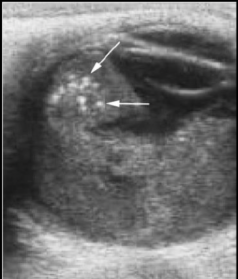

Q

El USG es útil para dx de retinoblastoma?

A

Sí, podemos ver lesiones hiperecogénicas con calcificaciones

Que estudio es y que se puede ver

USG que muestra retina doblada y brillante

29